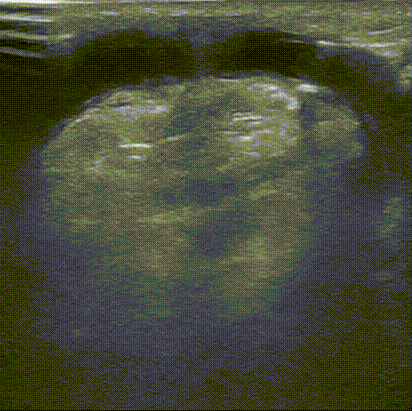

近吻合口4cm处, 内膜增生性狭窄S3,最小内径约1.7mm,相邻管径约3.8mm,范围约2cm。